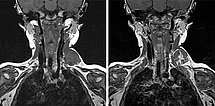

Die koronare MRT in T1-Wichtung, links vor und rechts nach Kontrastmittelgabe, auf gleicher Schnittebene zeigt die inhomogene, zu diesem Zeitpunkt noch unvollständige Kontrastmittelaufnahme sehr gut. Die Läsion nimmt langsam von zentral radspeichenartig KM auf.